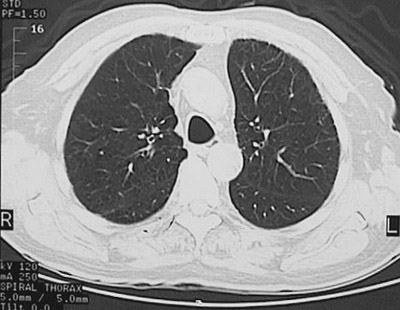

The CT scan of the chest seen here with a "lung window" reveals an increase in lung markings with lucencies consistent with centrilobular emphysema.